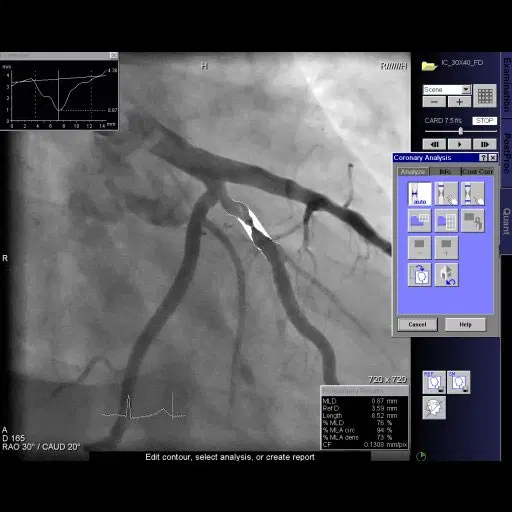

Innovative Diagnostic Devices

Partnering with Siemens Healthineers, we’re committed to patient care through cutting-edge imaging technology. Our offerings include an echocardiography system and general ultrasound for detailed organ and cardiac assessments. We also provide angiograms for comprehensive vascular insights, alongside our precise and versatile C-arm (mobile X-ray) for broader imaging needs. This integrated suite of tools empowers healthcare professionals with the detailed information vital for diagnosing, monitoring, and managing cardiovascular and other organ conditions, leading to improved patient outcomes and proactive health strategies

Advanced medical imaging, a vital diagnostic tool that visualizes internal organs and structures with precision. Our state-of-the-art technology empowers healthcare practitioners with essential insights, facilitating accurate disease diagnosis and effective treatment planning. Additionally, our Clinical Apps Specialist provides continuous support to ensure seamless utilization of our cutting-edge imaging system.